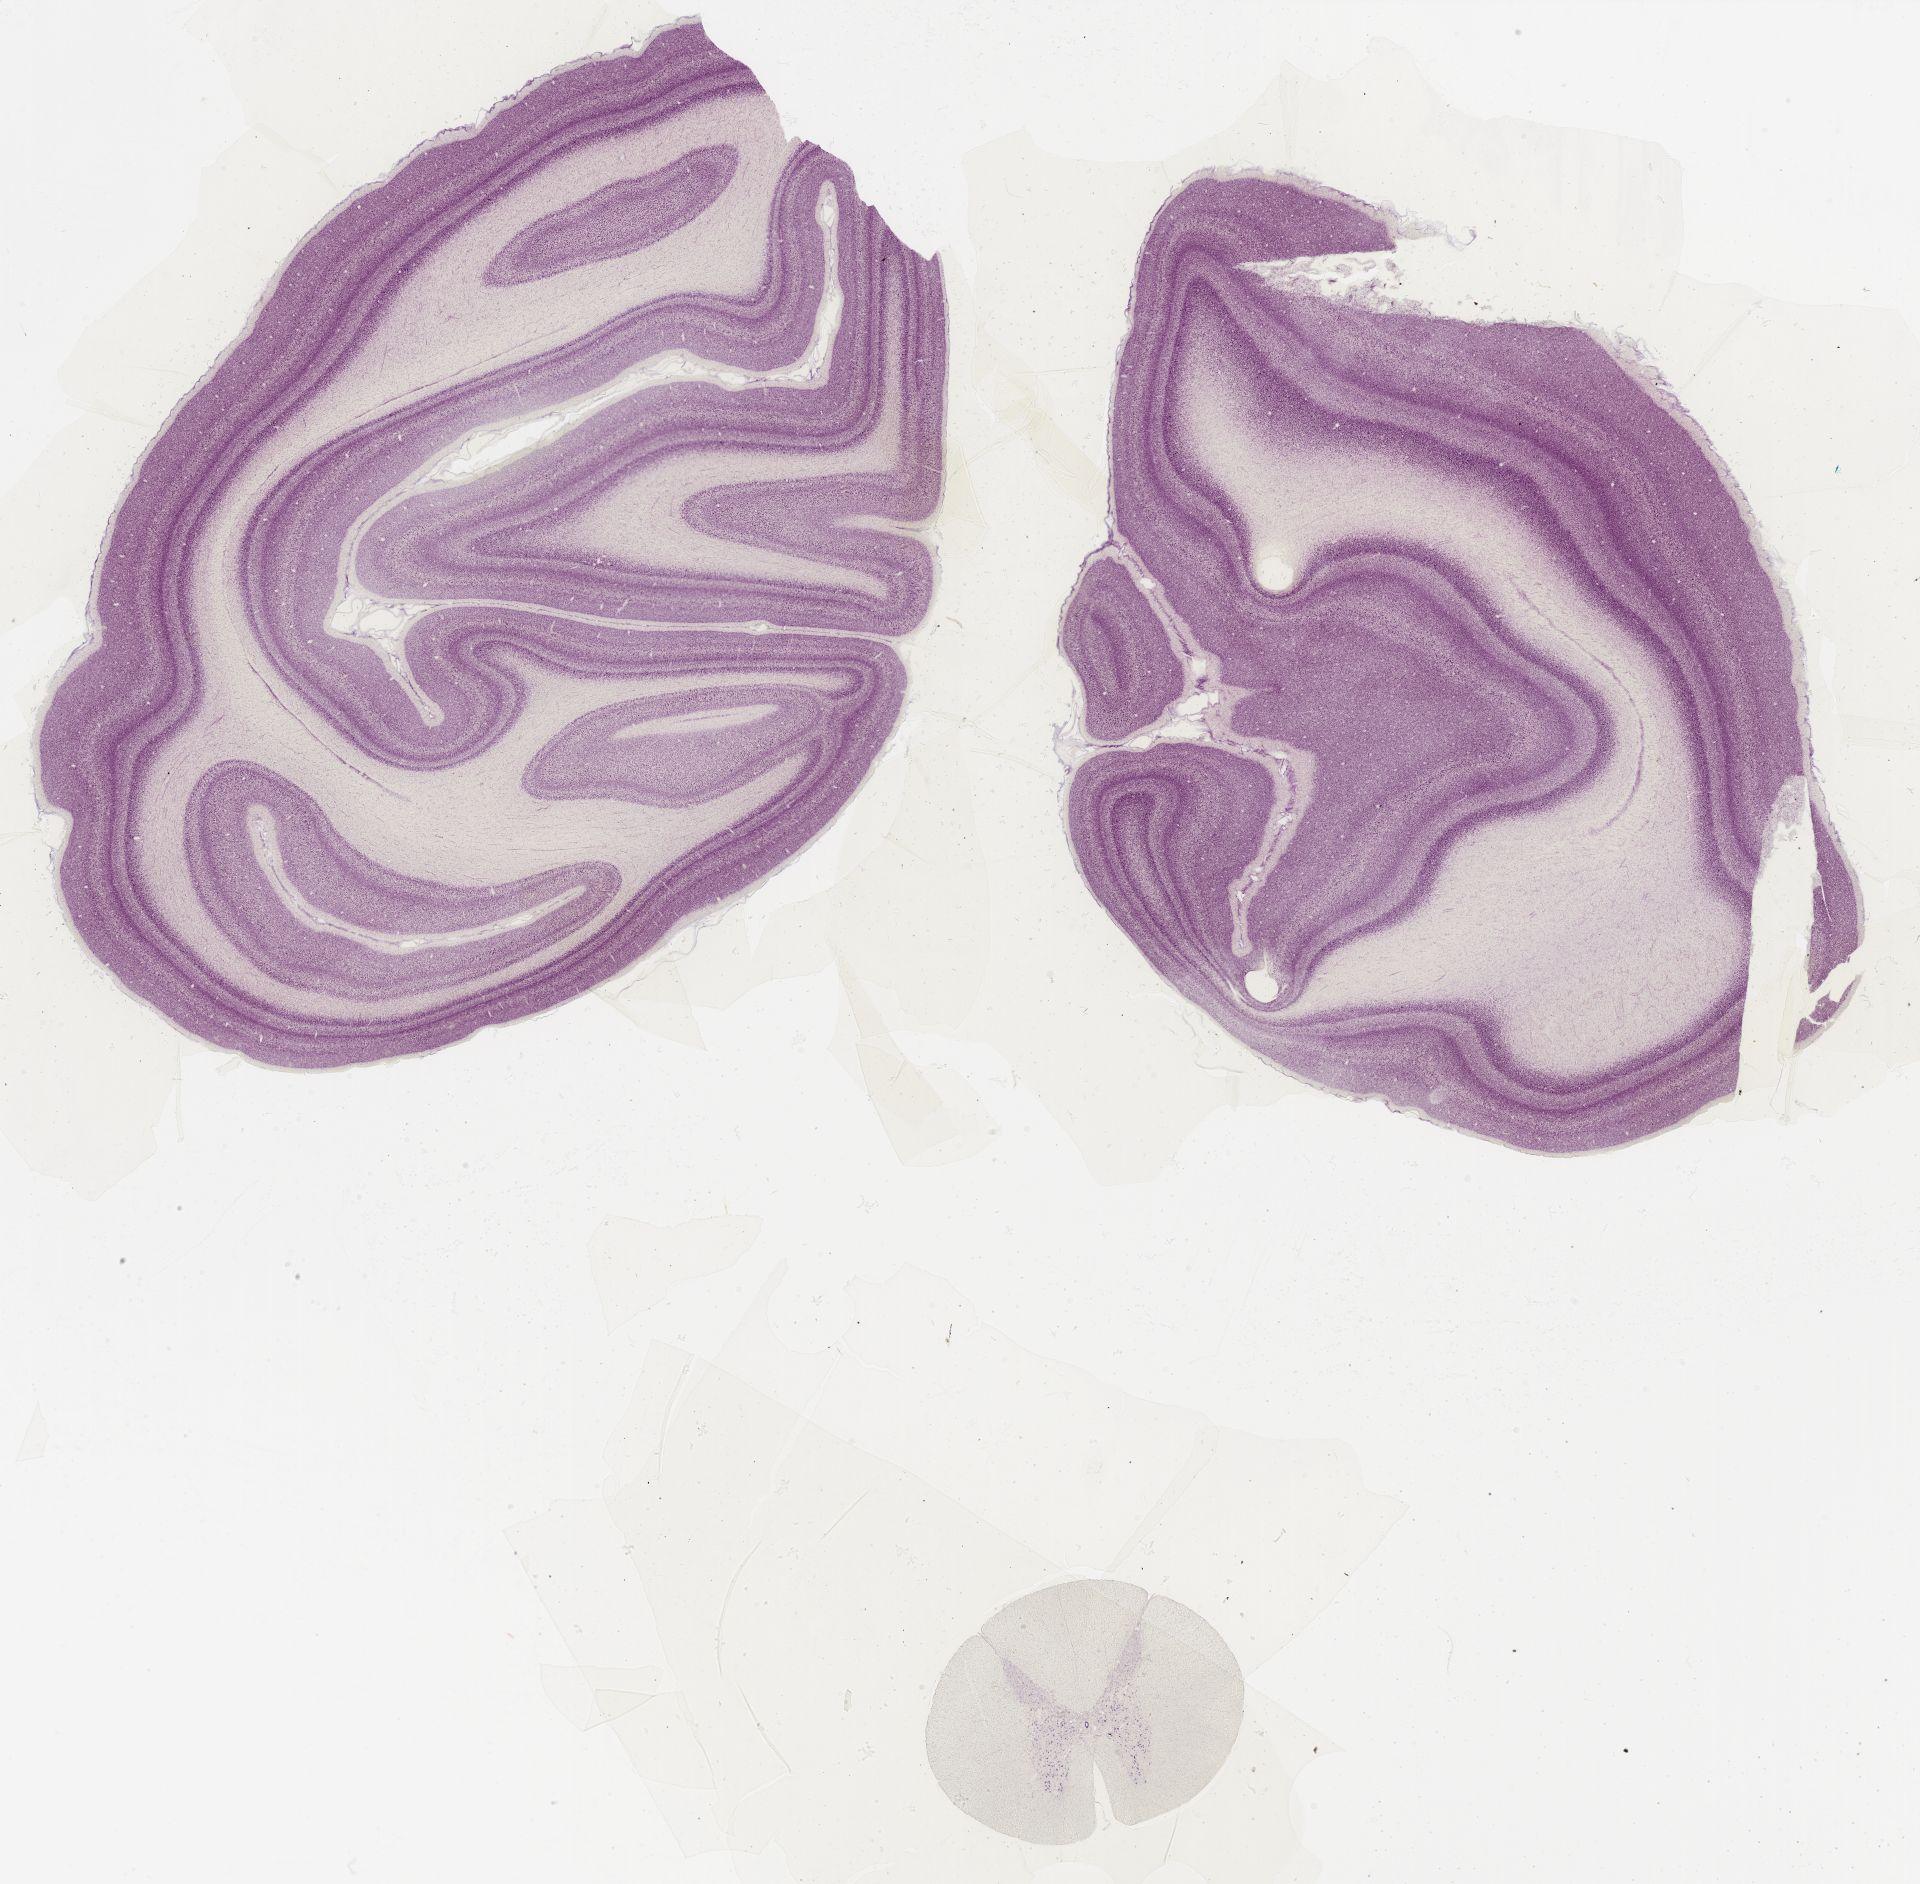

Datasets -> Macaca Mulatta -> Nissl, coronal, histo, Whole-Brain, adult

[ Metadata ]   ·   Source: Edward G. Jones

Displaying Sections 41 thru 56 of 56 Sections for this Dataset

0582 - labeled